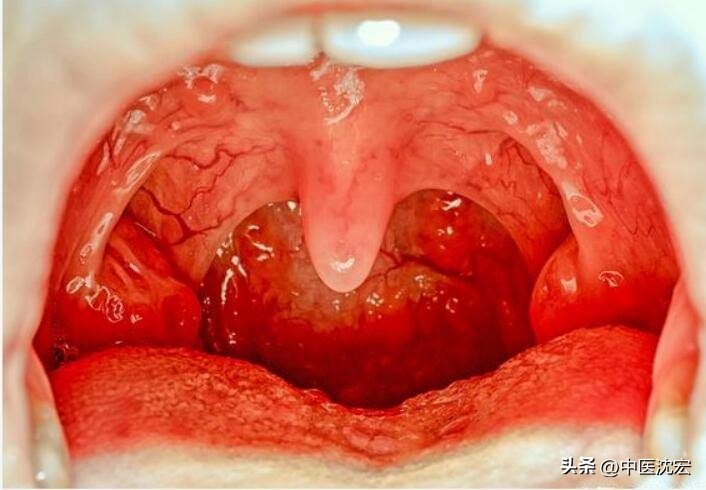

你有没有这样的情况,总是觉得嗓子不舒服,感觉有东西堵在那里,咳不出,咽不下,早上起床觉得嗓子又疼又干,喝了水也没有缓解,张大嘴巴发现嗓子都变红了,有时候长达几周都是这样。

在西医上这种情况被称为“咽炎”,在中医上就属于“喉痹”的范畴了。 一般都和肺燥,肾阴亏虚有关系。